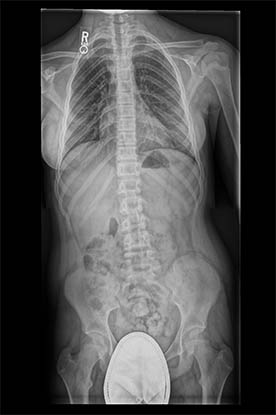

大长度成像支持采集椎骨和长骨影像,然后自动拼接多个(最多五个)探测器采集的影像。它代表了大长度成像领域速度和效率的新性能基准。